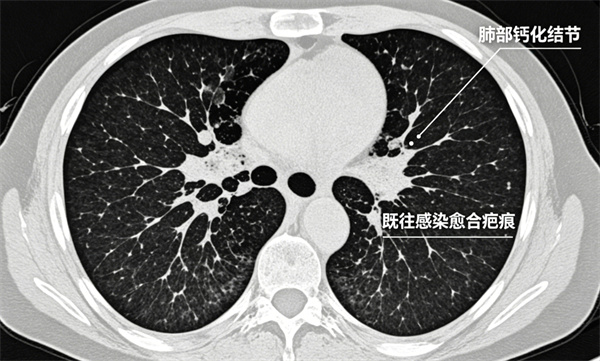

3钙化结节

多为既往感染愈合后留下的疤痕,类似皮肤痘印。

几乎都是良性,一般无需治疗、无需复查。